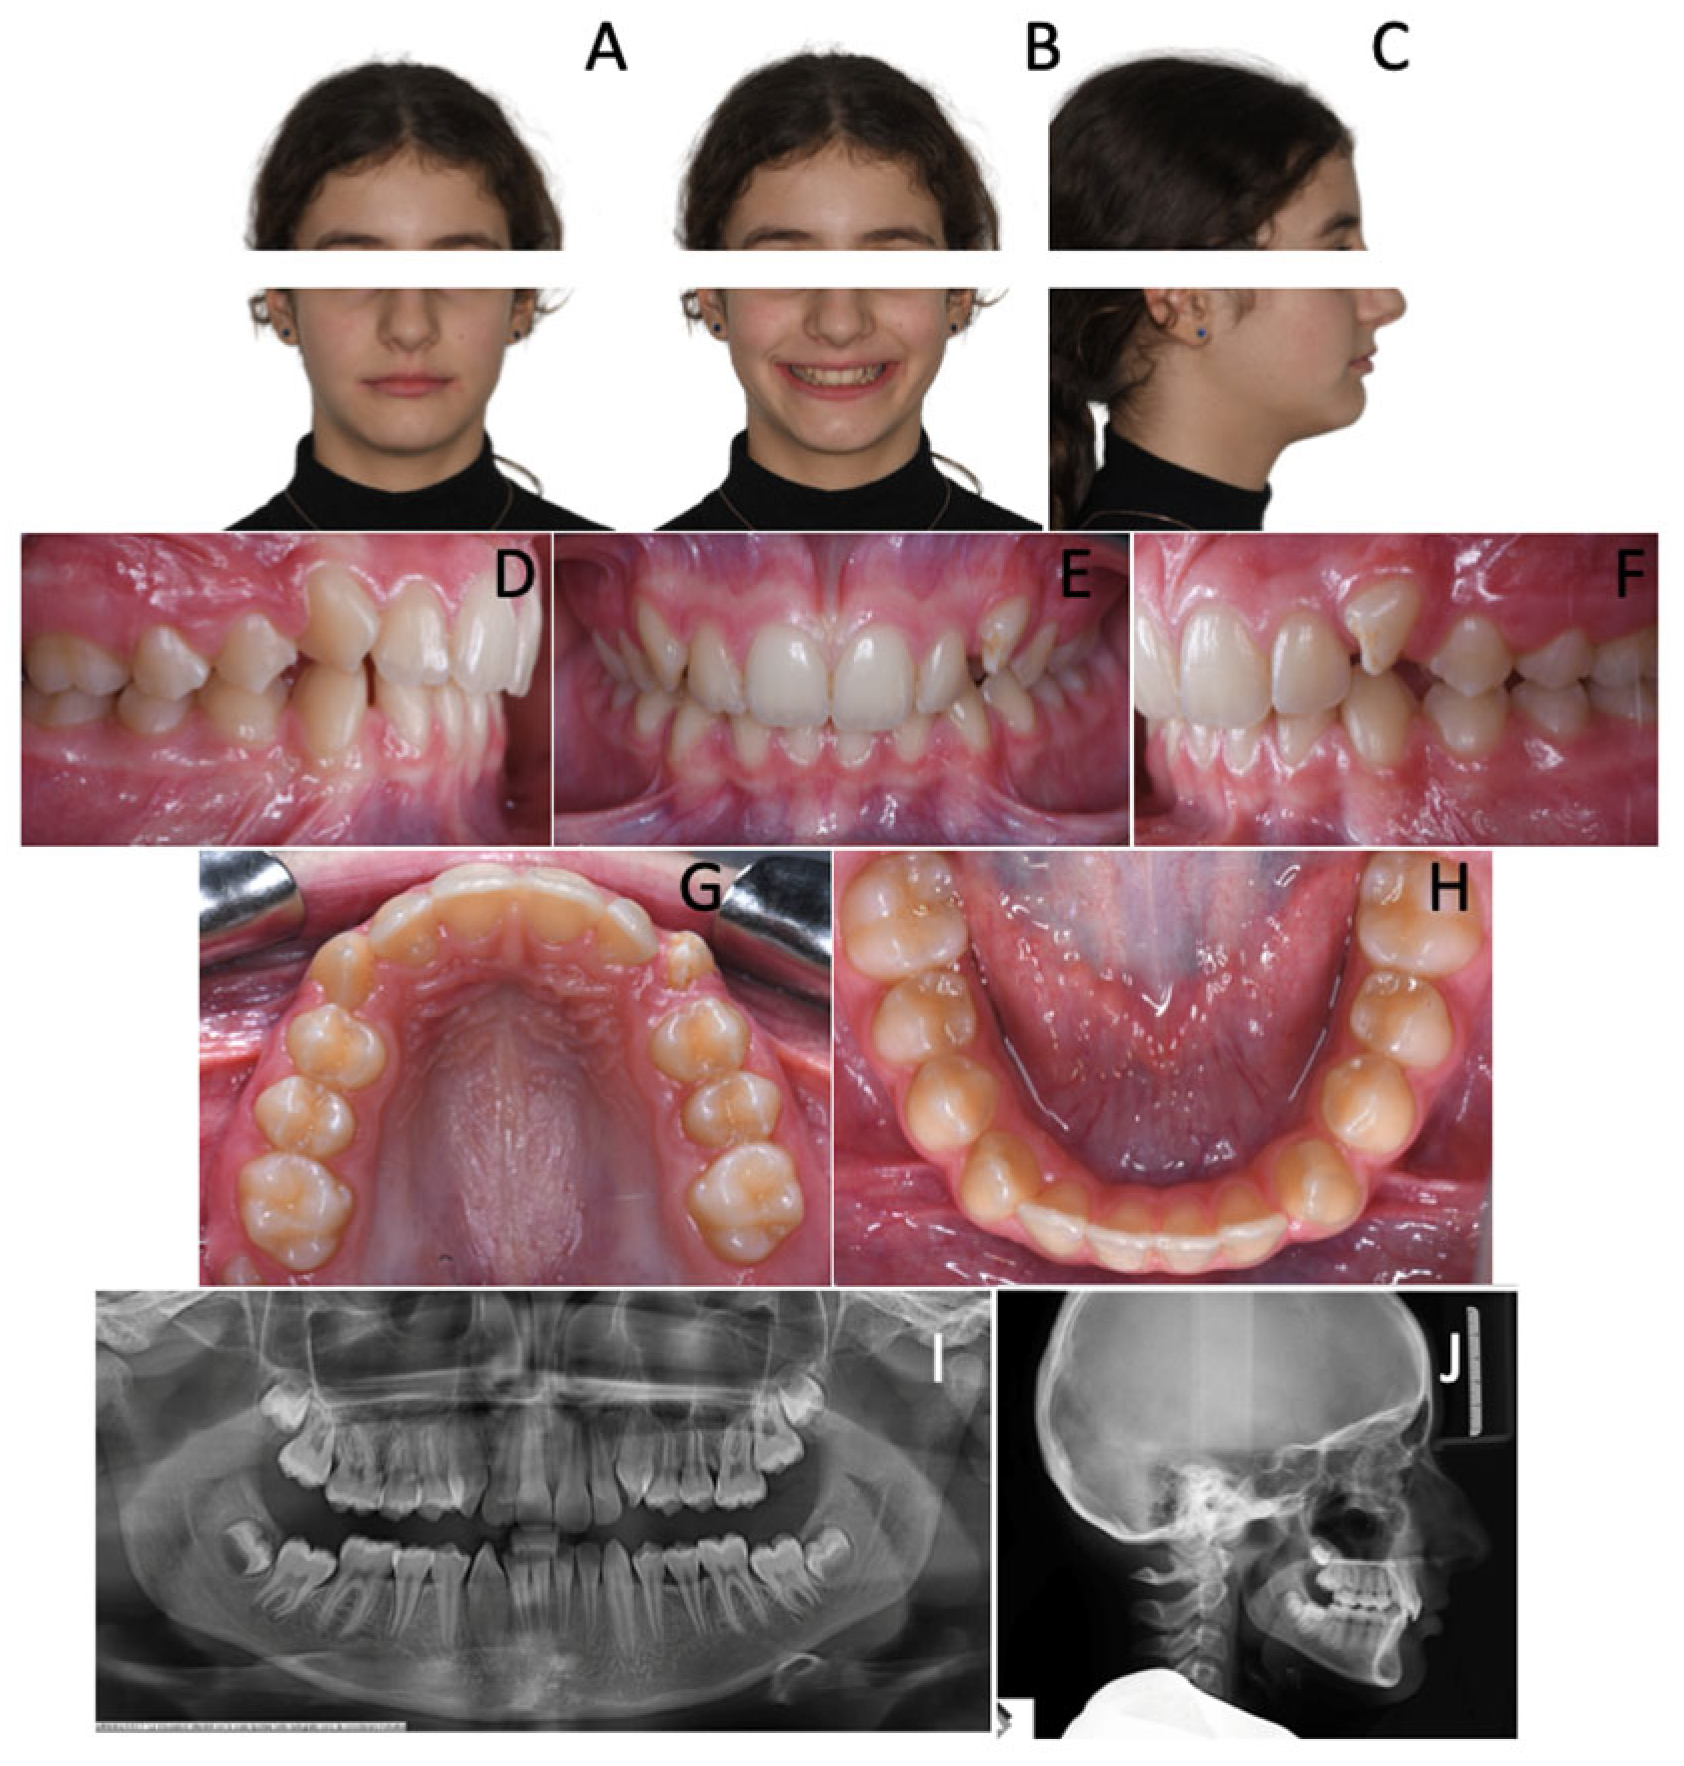

A 7-year-old female revealed early mixed dentition. Intraoral examination showed a symmetrical class II malocclusion (Figure 1) As a matter of fact, the upper and lower midlines were coincidental. Both the arches were constricted and the overbite was significantly decreased, resulting in an open bite tendency.

The lower arch showed significant anterior crowding. Indeed, the patient was noted to have six anterior mandibular teeth with fully developed clinical crowns: two central incisors, two lateral incisors, two supplemental teeth. Therefore, crowding was clearly due to the presence of two excess teeth.

The upper arch was slightly crowded and a lack of space for 1.2 and 2.2 was observed.

Figure 1. A 7-year-old female patient with two supplemental mandibular teeth. (AC) Extra-oral photopraphs; (DH) Intra-oral photographs; (I) Orthopantomography.